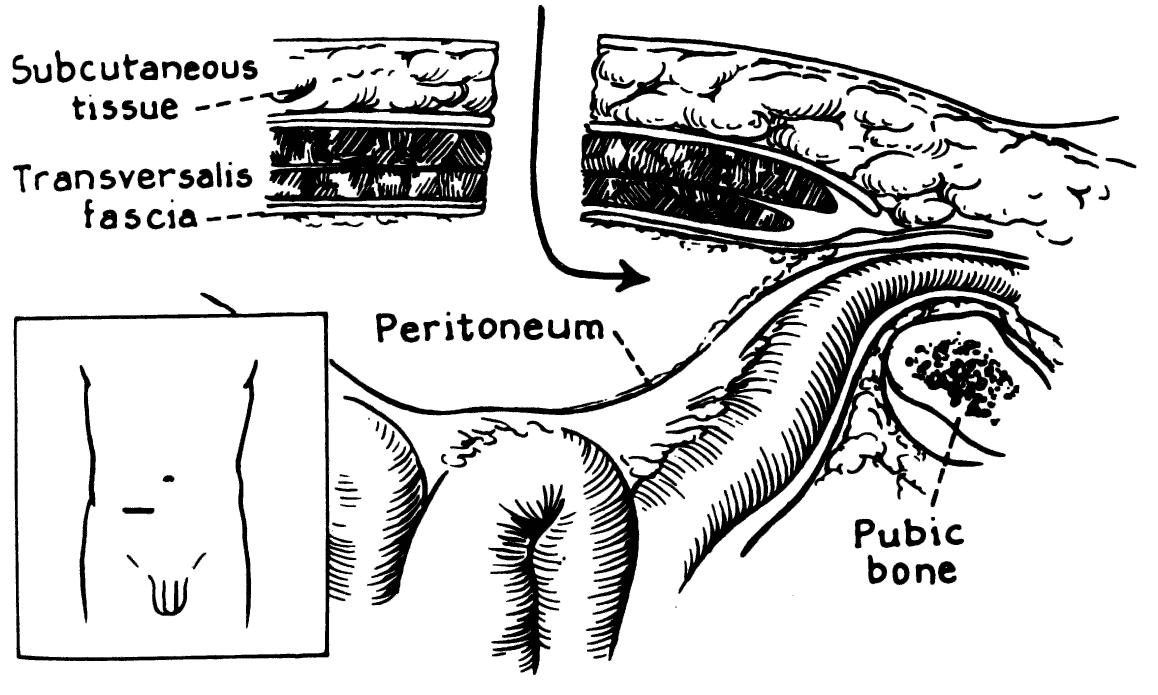

- The external iliac artery becomes the common femoral artery as it emanates from a point under the middle of the inguinal ligament.